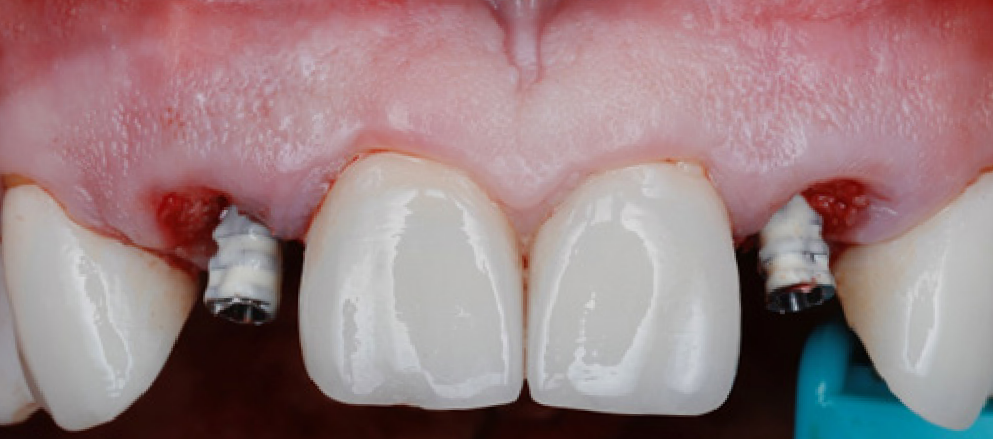

Upon delivery of the prosthesis, some blanching is a good sine of tissue compression in needed areas (usually proximally) which starts the process of tissue training.

After 3 months of tissue training, patient returned for his final evaluation prior to final restoration.